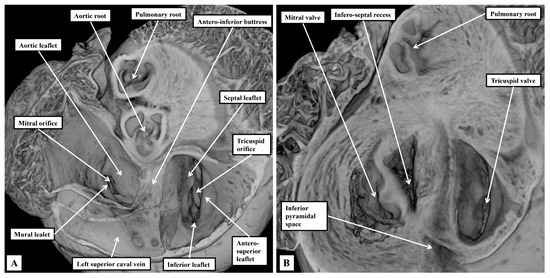

Background: Since the study of Lev and Thaemert in 1973, little has been published concerning the overall arrangement of the murine conduction tissues, in particular with relation to gross anatomical landmarks. We recently emphasised the potential va...